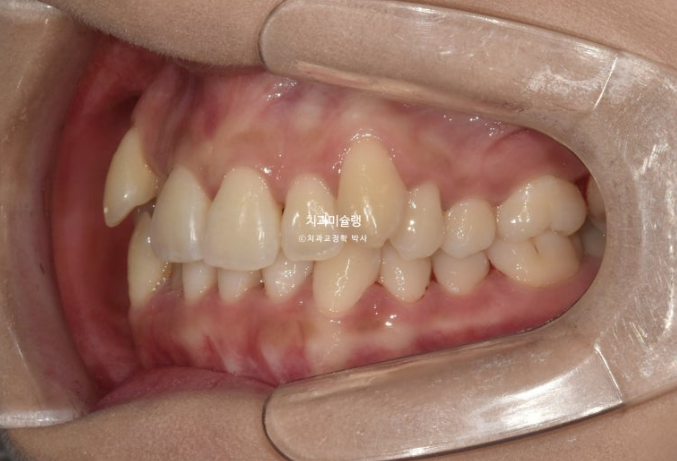

23.08

하악 사랑니 공간을 이용하여 덧니를 배열했습니다.